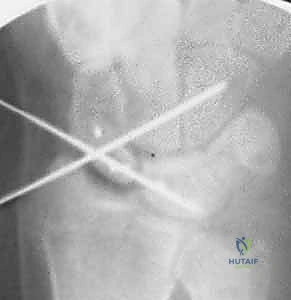

- Transarticular K-wire Placement: Once the joint is perfectly reduced, we will drive two 0.045-inch smooth Kirschner wires:

- Scapholunate Fixation: Drive one or two K-wires from the scaphoid into the lunate, traversing the reduced scapholunate joint. These provide primary stability to the repaired ligament.

- Scaphocapitate Fixation: Drive one or two additional 0.045-inch K-wires through the waist of the scaphoid into the capitate. This provides additional rotational stability to the scaphoid.

* Here, you can see the joint after reduction and SLIL repair. The Kirschner wires in the scaphoid and lunate are now parallel, correcting the DISI deformity. The transarticular K-wires are placed from radial to ulnar, passing through the scapholunate interval and scaphocapitate interval.

* An AP intraoperative fluoroscopic image demonstrating precise Kirschner wire placement across the scaphocapitate joint and the reduced scapholunate joint. Suture anchors are visible in the scaphoid at the dorsal SLIL footprint.

* A lateral intraoperative fluoroscopic image confirming accurate Kirschner wire placement and the reduced scapholunate joint. Note the suture anchors in the scaphoid.